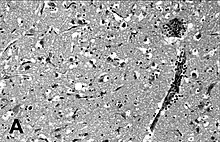

Image d'encéphalite à Phocine Distemper Virus.